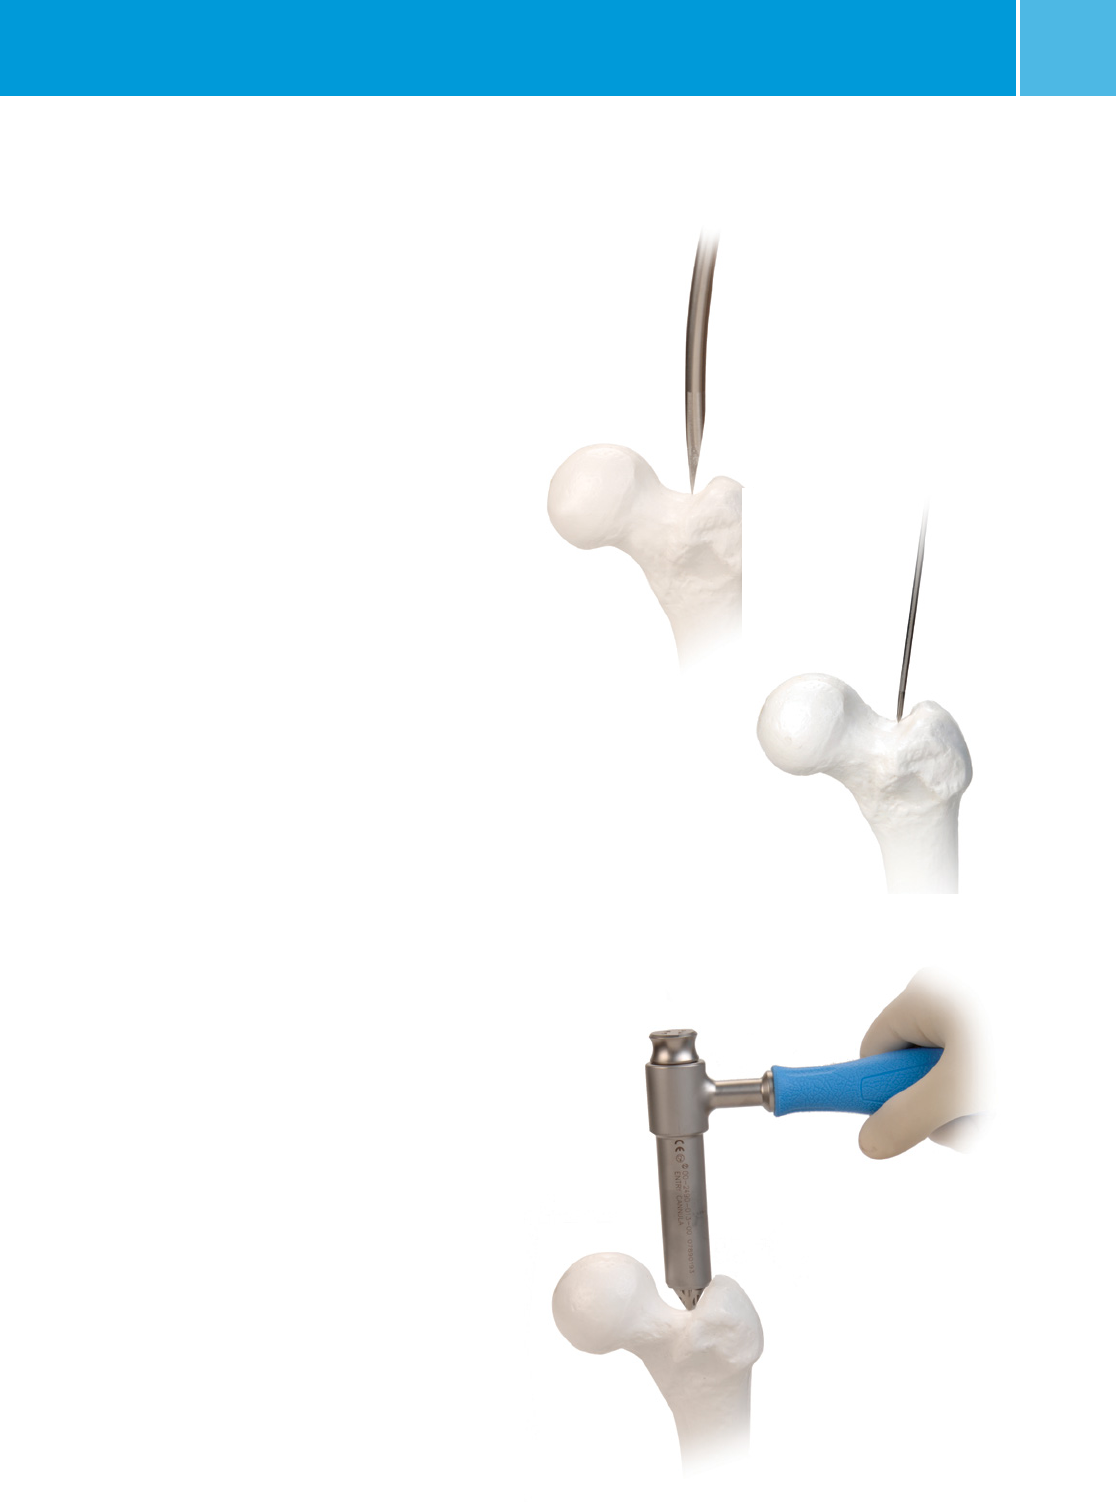

Place the 3.0mm threaded pin into the

starting point. Use the C-arm to visualize

the pin’s position from A/P and Lateral

views. The pin should be inserted at the

identified point in the direction of the

center of the medullary canal.

Drive the pin through the starting point into

the center of the medullary canal. Use the

8.0mm ENTRY REAMER to ream an entry

portal into the proximal femur through

the starting point (Figure 4). Remove the

reamer and 3.0mm pin.

Alternatively, an AWL can be used to find

the entry point and create the entry portal.

Place a 3.0mm x 100cm BALL TIP GUIDE

WIRE (00/47-2255-008-01) into the

medullary canal all the way into the distal

femur (Figure 5). To aid in manipulation,

bend the tip of the guide wire at about a

10 degree angle 5cm from the end.

CAUTION: If the guide wire is bent shorter

than 5cm from the end of the wire and/or

more than 10 degrees it may be difficult to

remove from the nail. If the wire becomes

lodged inside the nail, utilize the GUIDE

WIRE GRIPPER and mallet to remove the

guide wire from the nail.

Fluoroscopy can assist you in guiding the

wire past the fracture site. If you plan to

ream the canal of the femur, the ball tip

wire should be centered and embedded

in the distal femur at the level of the

distal epiphyseal scar using the GUIDE

WIRE GRIPPER and a MALLET (Figure 6).

Care should be taken not to drive the wire

through the distal femur.

Fig. 4

Fig. 5

Fig. 6

Fig. 7